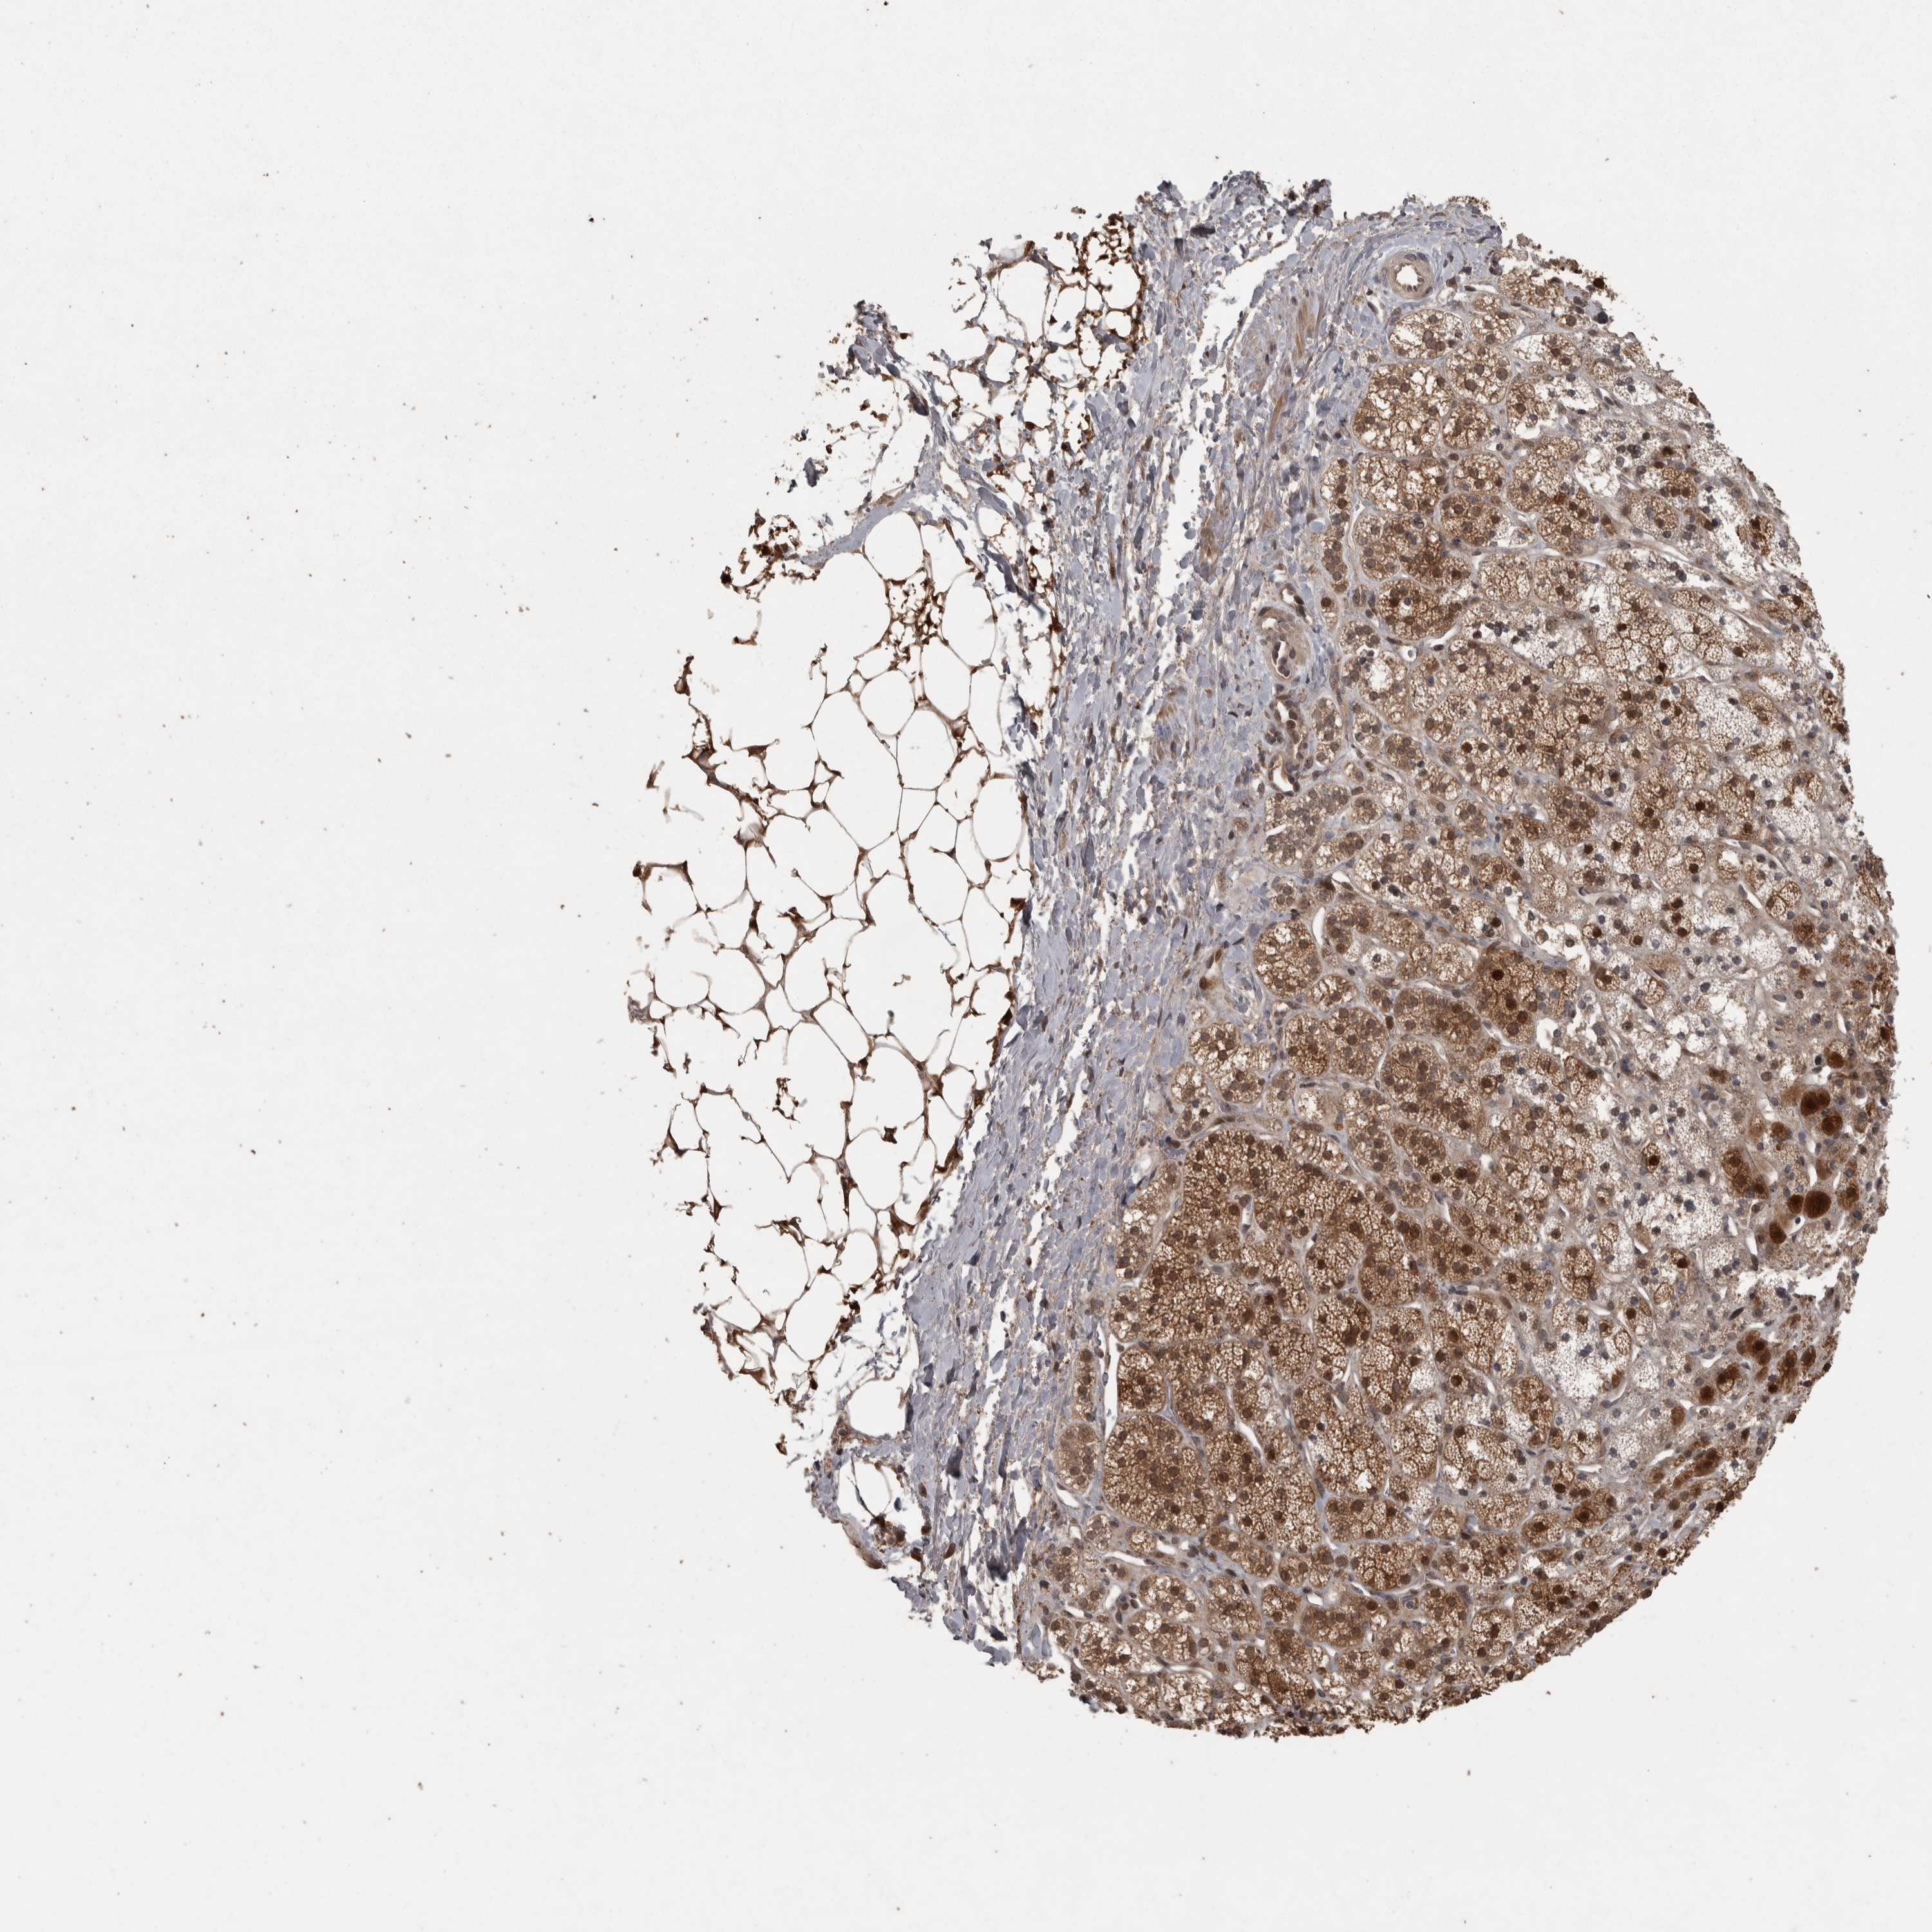

ADRENAL GLAND - Antibody stainingi

Antibody staining in the annotated cell types in the current human tissue is reported as not detected, low, medium, or high, based on conventional immunohistochemistry profiling in selected tissues. This score is based on the combination of the staining intensity and fraction of stained cells.

Each image is clickable and will lead to virtual microscopy that enables deeper exploration of all samples and also displays staining intensity scores, fraction scores and subcellular localization as well as patient and tissue information for each sample.

Antibody HPA019371Antibody HPA024157

Glandular cells MediumHigh